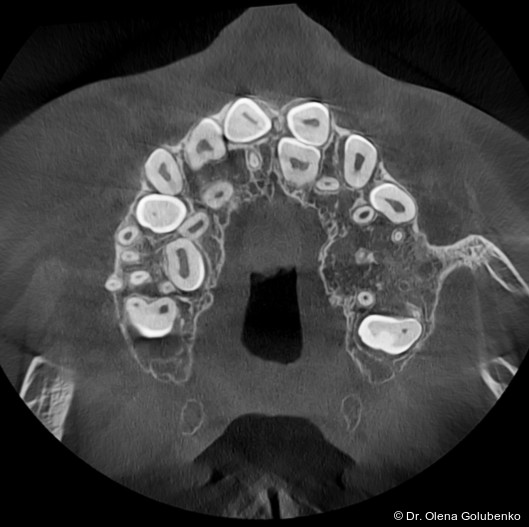

Die dreidimensionale Bildgebung zeigt meist eine hohe Anzahl nicht durchgebrochener permanenter und überzähliger Zähne, die in unterschiedlicher Lage im Kiefer verbleiben (Abb. 3+4).

Die Diagnostik der cleidokranialen Dysplasie basiert auf einer sorgfältigen klinischen Untersuchung, der Analyse von Panoramaaufnahmen sowie insbesondere auf der digitalen Volumentomografie (DVT). Ziel ist es, die Anzahl, Lage, den Entwicklungsstand sowie mög­liche Interferenzen der retinierten und überzähligen Zähne präzise zu erfassen und in ei­nen funktionellen sowie skelettalen Kontext einzuordnen (Abb. 5–8).